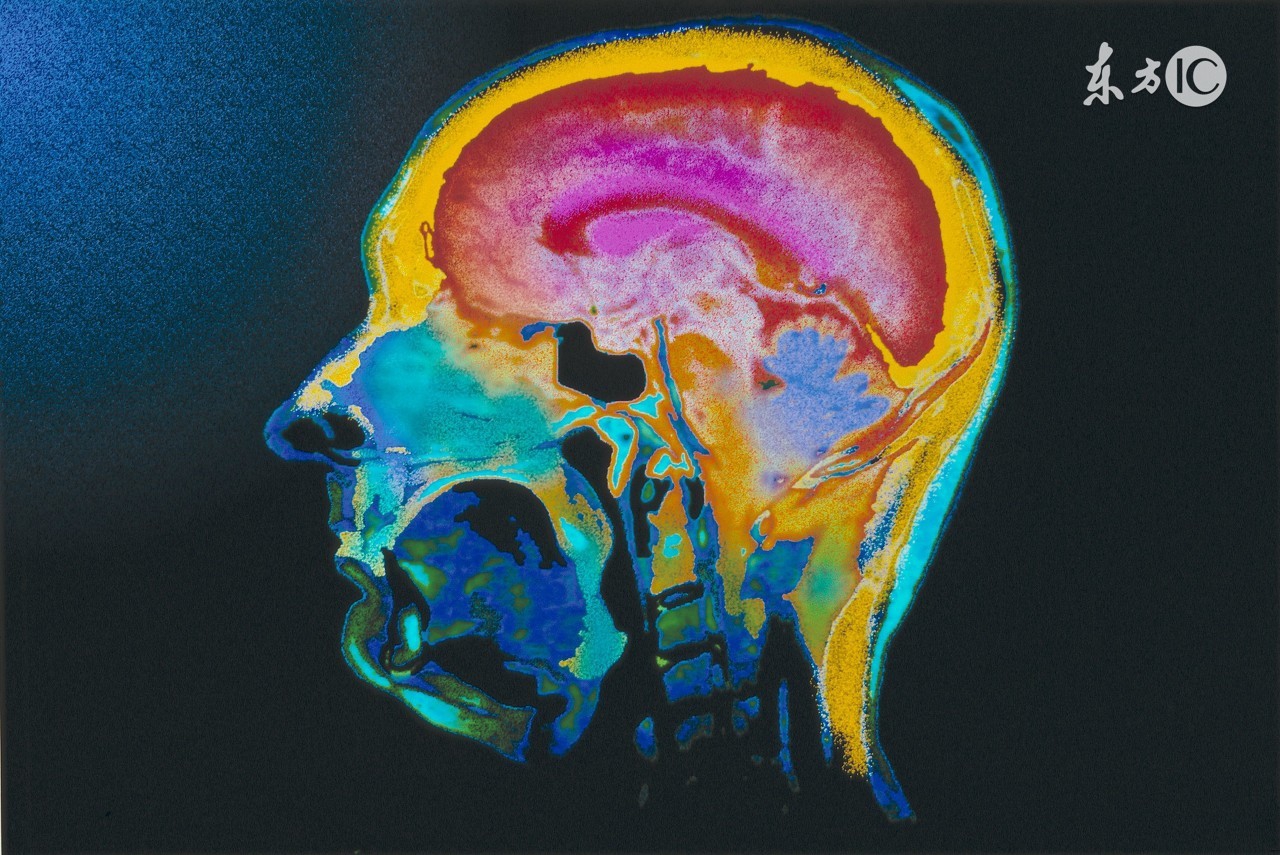

1. 不能认为头部外伤一定合并有脑损伤 临床上,只有头皮损伤或微小的颅骨线形骨折等都并不一定合并有脑损伤。因此,在强调头外伤患者应该警惕脑损伤的同时,并不主张泛化脑损伤的概念,造成伤者过多的思想负担。

2. 头部没有损伤却不一定没有脑损伤 脑组织就像一块装在硬盒子里面的豆腐,身体运动停止时脑组织的惯性运动是脑损伤的主要动因之一。譬如车祸中常见的脑组织“挥鞭样”损伤、坠落伤中臀部先着地导致的脑部“传递伤”等都属于这种情况。需要强调指出的是:车祸中的“挥鞭伤”很容易造成颈椎脱位,容易漏诊且处理不当会造成严重后果。

3. 颅内出血与否并不能决定伤情的轻重 意识障碍程度和持续时间可作为判断脑损伤病情轻重的指标,但那些仅凭检查结果未发现颅内血肿就认为病情轻微的观点是一个很严重的认识误区。事实上一些病情非常严重,治疗非常棘手,预后非常不乐观的脑外伤如脑干损伤、弥漫性脑损伤、轴索损伤等,往往仅有很少量出血或不伴出血。事实上,颅内出血与伤情的关系不但与出血量而且与出血速度和患者的具体情况有关。同样的血肿量,但出血速度较慢,脑组织的代偿功能来得及发挥,病情可以表现不严重,治疗效果和预后就比较好。反之就差。这样同样血肿量不同的治疗结局,与医生的治疗技术关系不大。一般来讲,就损伤而言,医务人员对原发的损伤无计可施,医生能够做的是避免、减轻或减缓继发性损伤,为原发伤的修复提供较好的条件。